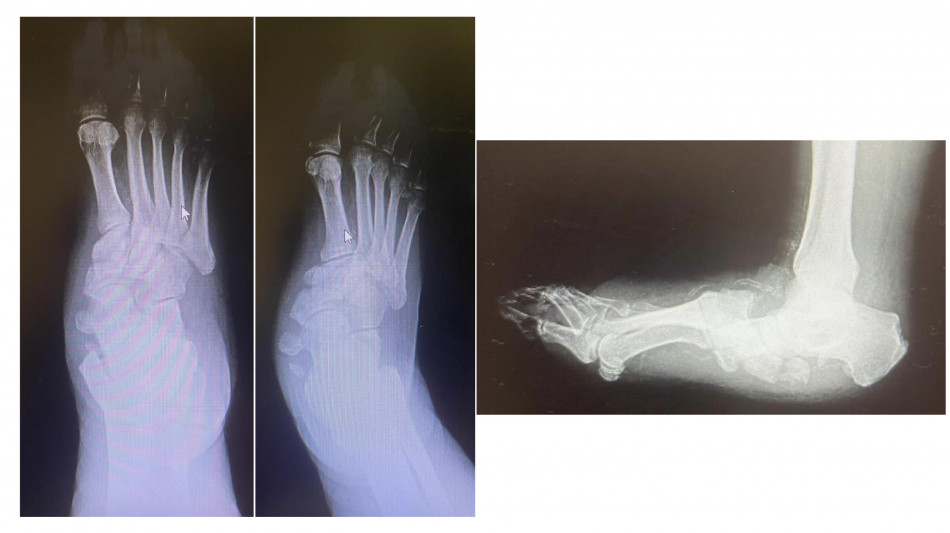

Tra le molte complicanze del diabete c'è anche il cosiddetto piede di Charcot (neuro-osteoartropatia di Charcot), una patologia rara ma gravemente invalidante e alto rischio di amputazione se non diagnosticata in tempo. Il policlinico universitario Gemelli di Roma è una delle poche strutture italiane dove è possibile gestire da un punto di vista internistico e diabetologico ed effettuare i complicati interventi di salvataggio ortopedico di questi piedi deformati e disabilitati. Condizione predisponente del piede di Charcot è la neuropatia diabetica. A essere affetto da neuropatia è almeno il 30-40% delle persone con diabete; il piede di Charcot compare solo nello 0,05% dei casi. "Questi pazienti hanno una grave disregolazione dei processi infiammatori, anche a seguito di uno stimolo banale, come il sovraccarico sul piede - spiega Dario Pitocco, associato di endocrinologia all'Università Cattolica del Sacro Cuore e direttore della Uosa di diabetologia della Fondazione policlinico Gemelli Irccs -. Molto spesso sono colpite persone che passano molto tempo in piedi (camerieri, cuochi) o che utilizzano molto il piede come gli autisti. Il fatto che la neuropatia attutisca il dolore fa sì che la diagnosi sia tardiva". Se questa fase diagnostica viene mancata, la malattia progredisce rapidamente verso la fase cronica. "Assistiamo a una progressiva alterazione dei tessuti molli, delle articolazioni e delle ossa del piede - spiega Carlo Perisano, ricercatore in ortopedia e traumatologia all'Università Cattolica del Sacro Cuore Campus e dirigente medico presso la Uoc di ortopedia e traumatologia del Gemelli -. Il piede si deforma fino a diventare un 'piede a dondolo', a causa della mal consolidazione dell'osso". Queste, in stadio avanzato, possono essere corrette solo da un complesso intervento, che di fatto diventa una chirurgia di salvataggio dell'arto. "Sono interventi che mirano a correggere deformità estremamente complesse del piede e della caviglia e che prevedono una serie di procedure chirurgiche (nell'ambito dello stesso intervento), quali osteotomie correttive e successive osteosintesi - prosegue Perisano - . Questo consente la ricostruzione di un asse del piede e della caviglia, per permettere al paziente di tornare a camminare".